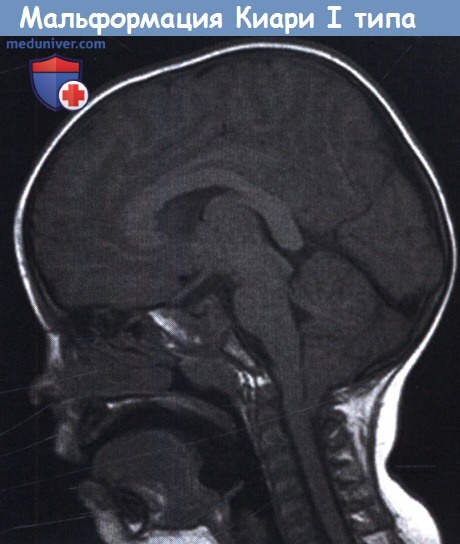

Аномалия Арнольда-Киари: MRI снимки